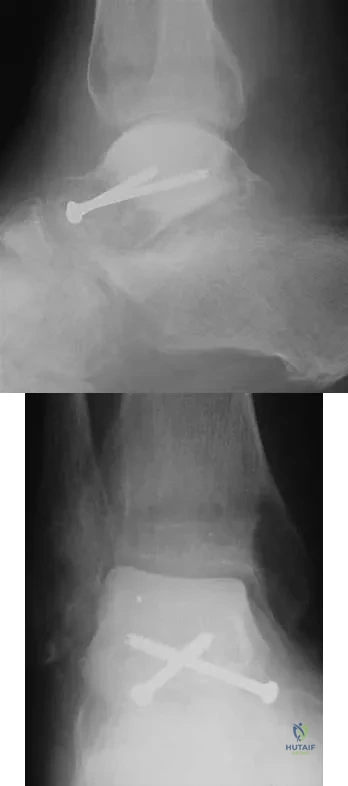

Question 64High Yield

A 45-year-old man is seeking evaluation of an injury sustained in a motor vehicle accident 10 weeks ago. Current radiographs are shown in Figures 2a and 2b. Based on the radiographic findings, what is the most likely diagnosis?

Explanation